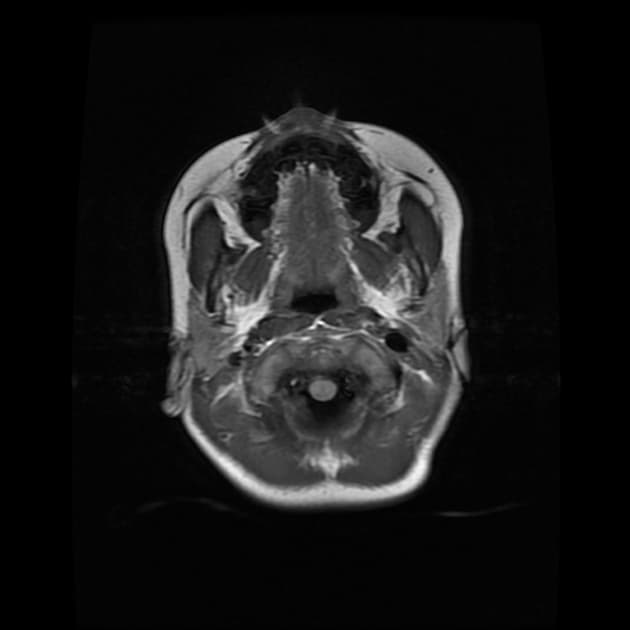

Chụp cộng hưởng từ (MRI) cho thấy các đặc điểm điển hình của bệnh xơ cứng rải rác. Ngoài ra, một số tổn thương có tín hiệu tăng trên hình ảnh T1 (T1 hyperintense).

Các phát hiện chính:

- Các tổn thương rải rác, dạng vệt hoặc hình tròn, tăng tín hiệu trên hình ảnh khuếch tán (diffusion-weighted imaging), khu trú chủ yếu ở vùng chất trắng quanh thất (periventricular white matter), chất trắng ở bán nguyệt (juxtacortical white matter), thân gai thị – giao thoa thị giác (optic radiation – optic chiasm), và thân não (brainstem) – phù hợp với đặc điểm của xơ cứng rải rác (multiple sclerosis).

- Các cấu trúc não sâu như các nhân nền (basal ganglia) và thùy đảo (insula) không bị tổn thương.

- Đa giác Willis (Circle of Willis) và các động mạch não trước (anterior cerebral artery), động mạch não giữa (middle cerebral artery), động mạch não sau (posterior cerebral artery) thông thoáng, không thấy tắc mạch (occlusion), bóc tách (dissection) hay tuần hoàn bàng hệ (collateral circulation) bất thường.

- Không thấy xuất huyết (hemorrhagic), tăng tỷ trọng (hyperdense) hay huyết khối thành mạch (mural thrombus).